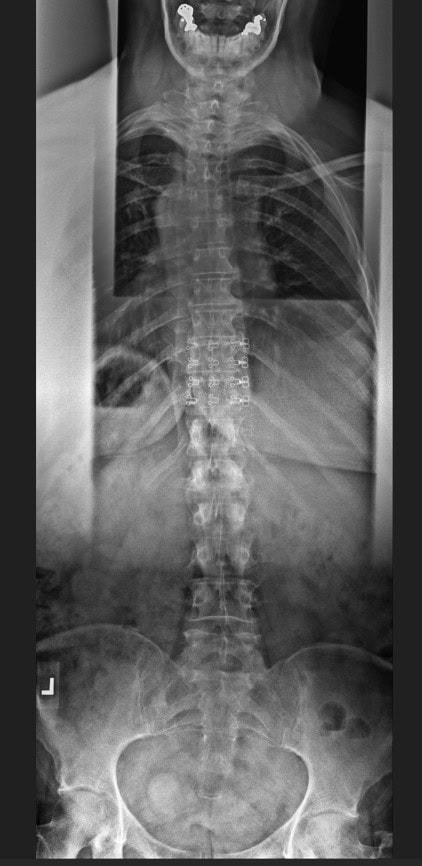

Post Scan